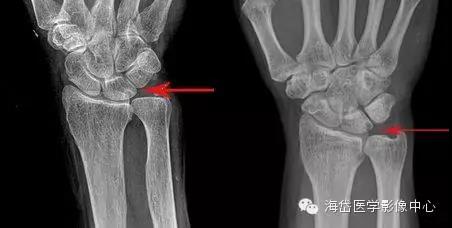

①X线:尺骨阳性变异(尺骨远端伸长)或处于中立位;月骨、三角骨坏死呈低密度小囊状改变以及月骨、三角骨关节面下软骨硬化,病变部位位于月骨尺侧近端和三角骨的腰部;尺骨小头相对关节面下软骨硬化或小囊性变。

其他X线表现包括桡骨远端骨折畸形愈合,桡骨远端异常背倾畸形和桡骨近端骨折畸形愈合导致桡骨缩短,尺桡远侧关节脱位。因为尺骨头与月骨解剖位置邻近,易发生撞击且易形成桥连状态(尺骨头与月骨连接)而产生持久性压迫,因此在尺骨阳性变异的患者中月骨发病率明显大于三角骨。

X线测量:在标准后前位X线平片测量尺骨变异,采用Gelberman等的平行线法(尺骨头关节面的平行线与乙状切迹最远端关节面的平行线之间的位置距离差)。